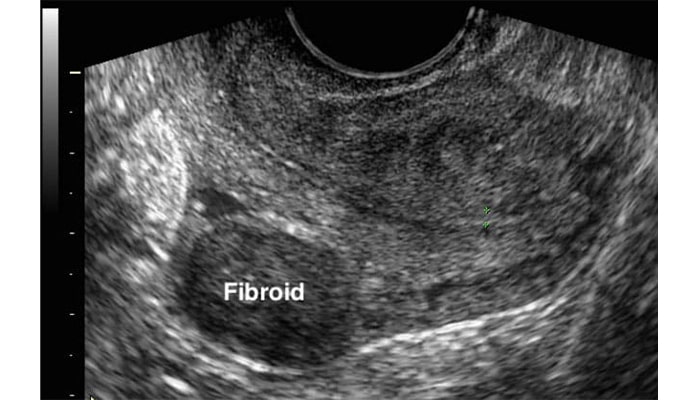

عکس فیبروم رحم در سونوگرافی

امروزه تشخیص فیبروم های رحم با روشهای مختلفی انجام می شود. لازم به ذکر است انتخاب روش تشخیصی به عوامل مختلفی اعم از شدت علائم ، اندازه فیبروم ها و وضعیت بیمار بستگی دارد. برخی از روشهای تشخیص این عارضه به شرح زیر است:

- سونوگرافی